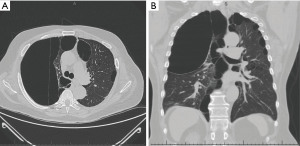

A 63-year-old man with GPB and a history of left-sided bullectomy in 1986 was lost to follow-up but presented in 2021 after a motor vehicle collision. On admission, he endorsed progressive dyspnea on exertion that predated the crash. CT scan demonstrated a giant bulla occupying >50% of the right thorax, causing ipsilateral atelectasis and contralateral tracheal shift (Figure 1). Also present was a right-sided pneumothorax and a left-sided hilar mass. The patient underwent inpatient bronchoscopy with biopsy of the hilar mass, which was negative for malignancy. His pneumothorax was managed with a chest tube, and he was discharged.

Over the next 1.5 years, the patient reduced his smoking and participated in pulmonary rehabilitation. His PFT at this time demonstrated moderately severe obstructive airway disease (Table 1). Repeat CT imaging showed minimal change in the size of his large bulla (Figure 2). The patient continued to follow up in clinic for another 8 months without a significant change in his imaging, PFT, oxygen requirement, or symptoms. He presented at this time for elective VATS bullectomy and wedge resection. His giant bulla was visualized to be located in the right upper lobe and occupied >50% of the hemithorax. This was removed and sent for pathology, which was consistent with lung parenchyma. The patient was also noted to have medium-sized bullae present in the right middle lobe. Two wedge resections were performed to remove this diseased tissue. The patient tolerated the procedure well. Two chest tubes were placed, which were removed three days post-operative (post-op). Follow-up chest X-ray two weeks later demonstrated expansion of the right lung without evidence of giant bullae or pneumothorax (Figure 3, Table 2).